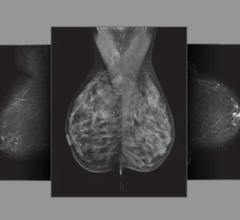

June 4, 2024 — Using artificial intelligence (AI), breast radiologists in Denmark have improved breast cancer screening ...

May 28, 2024 — iCAD, Inc., a global leader in clinically proven AI-powered cancer detection solutions, announced a ...